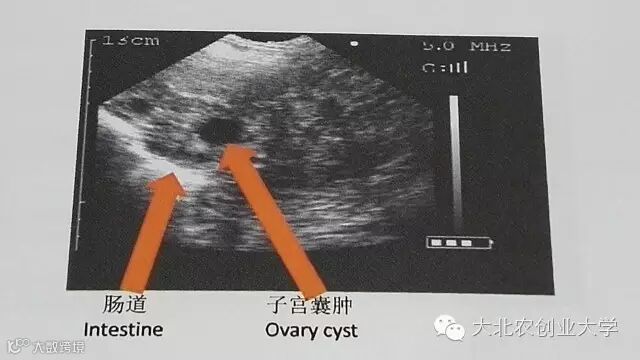

B超检测图片讲解

问题二维图像

探头位置不正确

总结:

1、常见的误诊来源是将黑点误认为胎囊,或将子宫内液体形成的小黑点误认为早期妊娠;